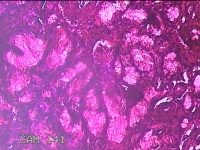

左侧鼻腔新生物

性别

女

年龄

43岁

临床诊断

1.慢性鼻窦炎 2.鼻息肉 3.鼻中隔偏曲 4.鼻腔粘连 5.变应性鼻炎

一般病史

鼻塞、脓涕3月余。’

标本名称

大体所见

灰白暗红色不规则肿物1.3x0.3x0.2cm一个,表面糜烂,内有少许骨质。

图2